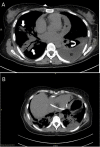

A 44-year-old previously well woman presented with features of respiratory sepsis including a productive cough and fevers, with a recent preceding influenza-like illness. She was diagnosed with community-acquired pneumonia on chest radiograph, influenza infection via nasopharyngeal swab and Streptococcus pneumoniae bloodstream infection with associated purulent pericarditis. She was managed with pericardial drainage and concurrent treatment with antibiotics and made an excellent recovery. This case highlights the complications of both influenza and S. pneumoniae infections, and the importance of prevention via vaccination.